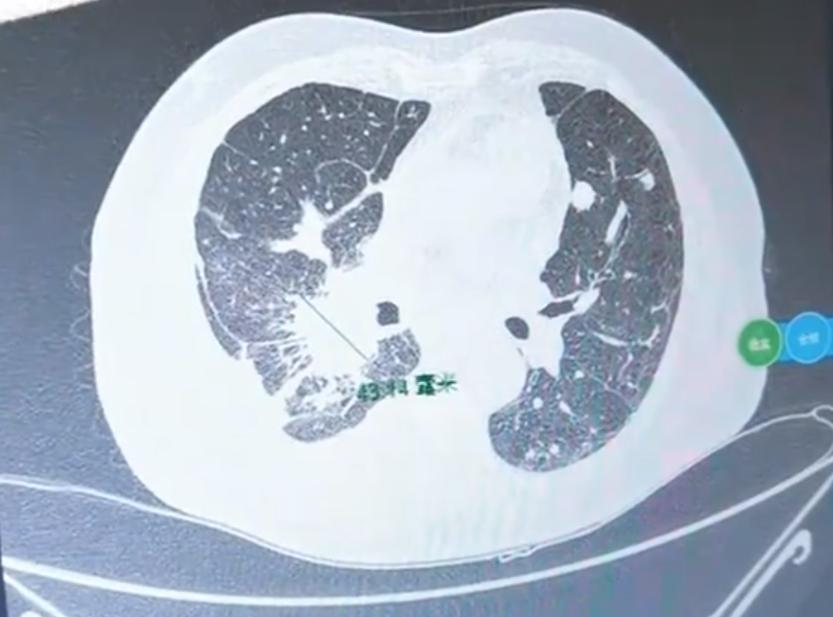

说到肺癌的基因检测,相信很多朋友都纠结过:做吧,得自己掏钱,常常要花几千甚至两三万;不做吧,又怕耽误病情。尤其是最近有朋友问我:“查出肺鳞癌,到底要不要做基因检测?” 其实,做基因检测的主要目的,是为了匹配靶向药。如果检测到特定的基因突变,又有对应的靶向药可用,治疗效果往往比较好,尤其对于晚期肺癌患者,医生通常都会建议做一下。 不过,肺鳞癌和肺腺癌的病理类型不同,基因状态也差异很大。肺腺癌患者中,超过一半能找到相关的基因突变靶点; 而在肺鳞癌中,基因突变的发生率很低,一般不到5%,也就是说,绝大多数肺鳞癌患者是找不到靶向药的。 那如果已经确诊肺鳞癌,还要不要做基因检测呢? 说实话,从匹配靶向药的角度来看,确实大概率用不上。但也不是完全没必要做——这时候检测的目的,就不只是为了找靶向药了。更关键的是,可以通过检测基因突变的复杂程度,来预测免疫治疗的效果。 通常,突变越多、越复杂,对免疫治疗的反应可能就越好。 目前,对于肺鳞癌,临床上常用化疗联合免疫治疗的方法,大约70%的患者肿瘤能得到控制,甚至明显缩小或消失。当然,这只是一个总体概率,具体到每个人身上,效果还是会有差异。 所以,要不要做基因检测,最终还是得结合自身病情、经济条件和治疗意愿来权衡。 如果条件允许,做个检测可以为治疗选择提供更多参考;如果负担比较重,也可以先和医生充分沟通,也可以不做。[作揖][玫瑰]